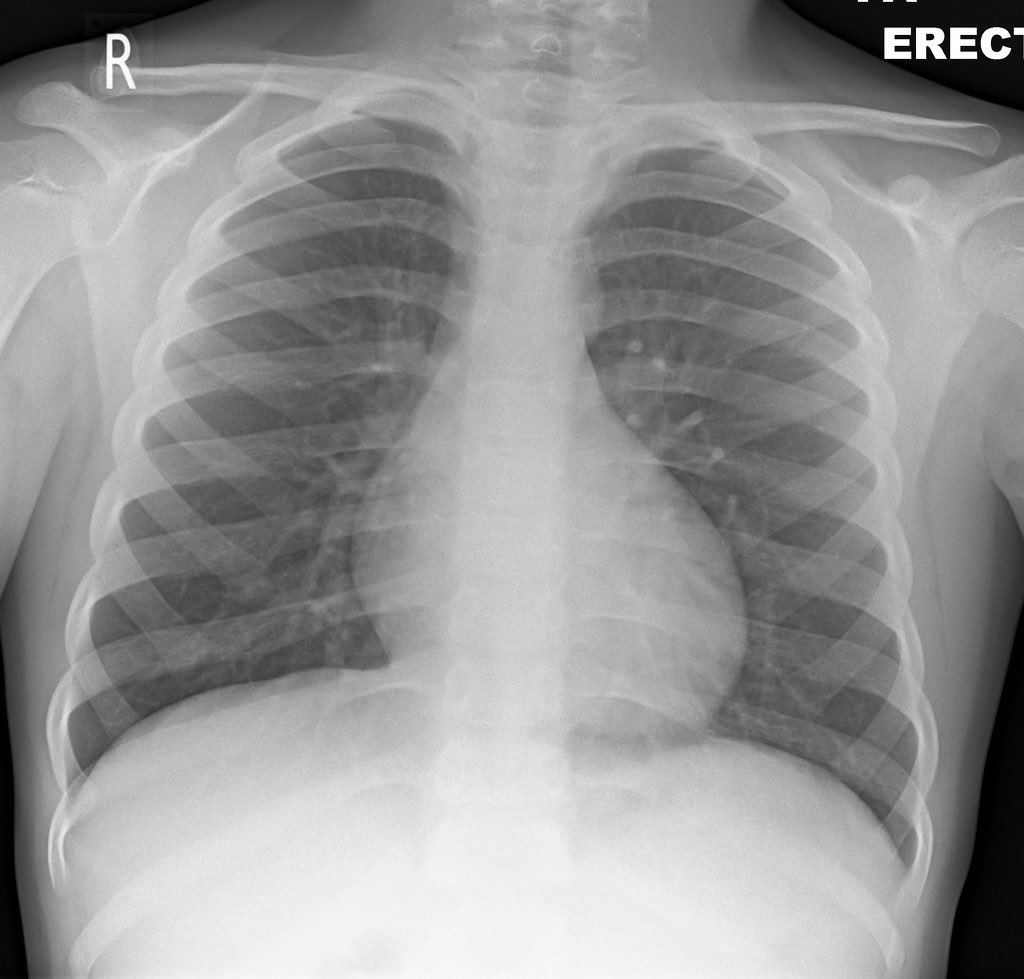

اليسار (طبيعية)

اليمين (التهاب الرئة)